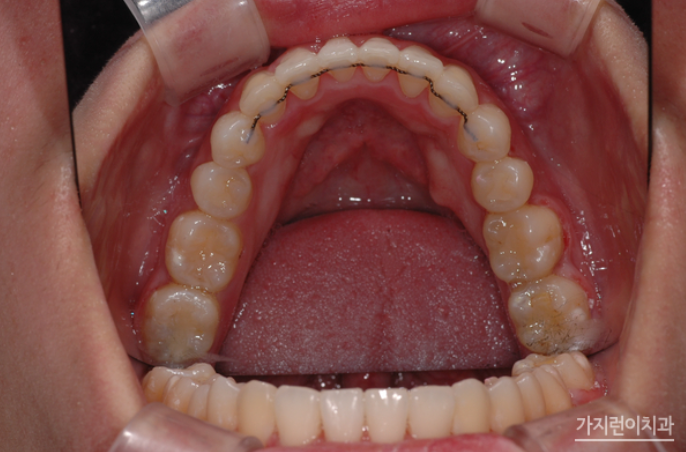

위 환자의 경우 상악 돌출입 증상과 더불어 심한 충치로 인해 발치가 불가피한 악조건을 갖고 있었는데요. 충치는 정도가 심하면 결국 발치를 하게 되고 인공치아를 식립해야 하는 과정을 밟게 되는데요. 그런데 환자의 경우 불규칙적인 치열의 재배열과 더불어 콤플렉스로 자리잡은 돌출입도 교정으로 진행해볼 수 있었습니다. Modified Bonded Cantilever Spring (MBC spring) 교정으로 사랑니에 직접 부착해 사랑니를 세우는 교정을 진행하게 되었는데요. 사랑니가 쓰러져 있는 상태라면 기존의 교정장치를 부착하기 어렵기 때문에 개발된 장치를 사용하고 있습니다. 그러면 장치를 착용한 후의 경과를 볼까요?

하지만 사랑니를 세우는 교정이라고 해서 모든 사람이 Modified Bonded Cantilever Spring (MBC spring) 교정을 사용하지는 않는데요. 환자분의 경우 하악 어금니 발치 공간을 메우는 과정에서 사랑니가 쓰러져 있긴 했지만 교정장치를 부착할 수 있는 상황이었기 때문에 추가적으로 Modified Bonded Cantilever Spring (MBC spring)을 사용하지는 않았습니다. 대신 돌출입 해결을 위해 상악을 후방으로 이동하기 위해 교정용 스크류를 이용해 진행하게 되었는데요. 총 2년 3개월의 치료기간이 소요된 환자분의 교정전후 사진을 확인해볼까요?